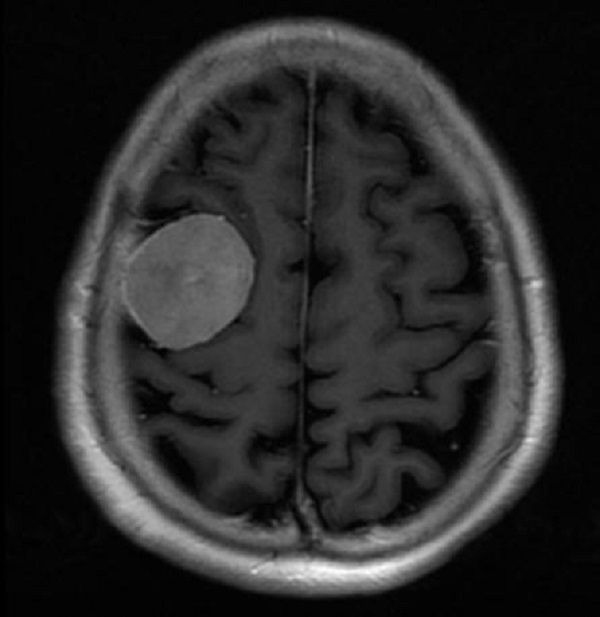

近日,二一五医院神经重症监护室谢国强主任团队成功应用3D打印导板技术,为一例患有颅内肿瘤患者规划了个体化手术方案,精确定位肿瘤部位,在显微镜下全切肿瘤。 63岁的李女士以“间断性头痛、头晕3周”主诉入院。头颅CT及MRI提示:右额叶占位病变,病灶呈均匀强化,可见脑膜尾征,考虑脑膜瘤。

术后CT: